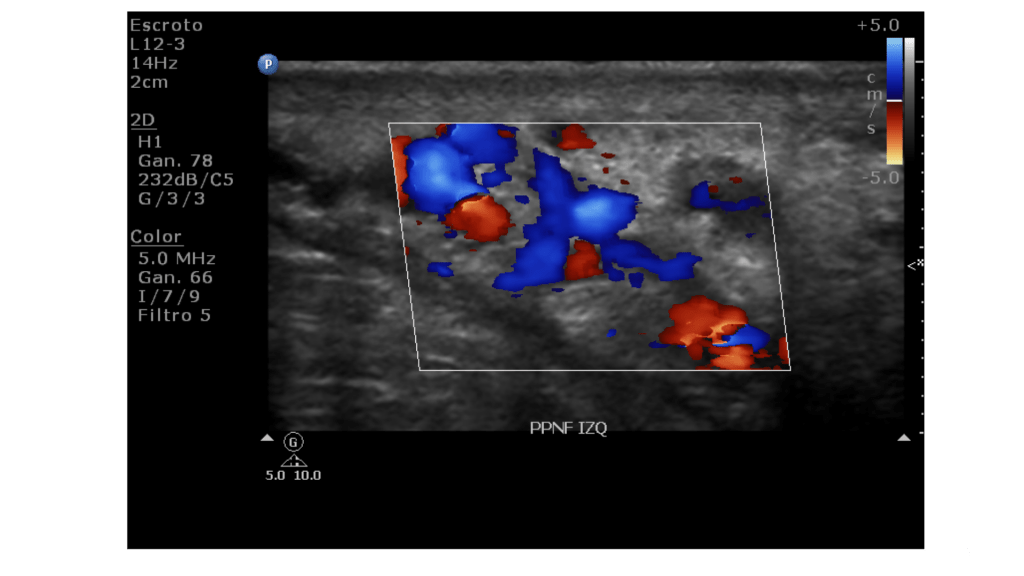

Criterios Ecográficos y Doppler Color

La ecografía Doppler es la modalidad de imagen de elección para confirmar el diagnóstico y evaluar la severidad hemodinámica.1 Se considera diagnóstico un diámetro venoso superior a 3 mm en bipedestación o durante la maniobra de Valsalva.1 El uso del Doppler pulsado permite cuantificar el flujo retrógrado; un reflujo que persiste por más de 2 segundos durante el Valsalva se asocia consistentemente con anomalías venográficas y daño testicular.1